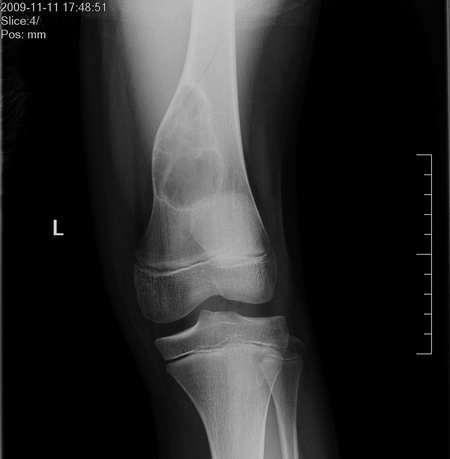

男,13岁,因膝关节外伤来照片,伤前无症状。

干骺端病变,透光度较高,有明显硬化边,内多房分隔,无明显钙化,可见骨皮质裸露征,无骨膜反应及软组织肿块,男13岁,考虑良性肿瘤样病变,多房性骨囊肿可能。

鉴别:abc、nof、软黏纤、囊性骨纤。

建议ct。